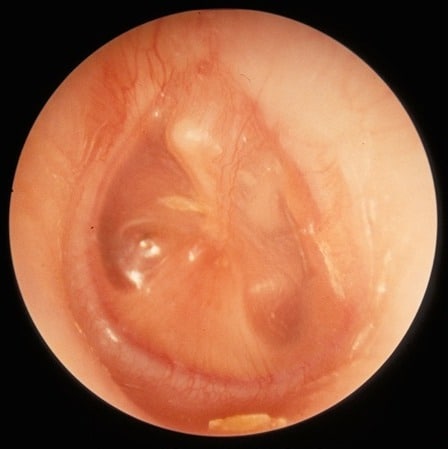

Myringotomy with grommet, also known as tympanostomy or ear tube surgery, is a common surgical procedure performed to alleviate ear conditions that affect the middle ear. The ear surgery involves creating a tiny incision in the eardrum to drain any accumulated fluid and insert a small ventilation tube, known as a grommet or ear tube. This allows air to enter the middle ear, equalizing pressure and preventing fluid buildup. Myringotomy with grommet is often recommended for patients experiencing recurrent ear infections, chronic otitis media with effusion (OME), and hearing loss due to fluid retention.

- Tympanosclerosis: A harmless condition where the eardrum develops a whitish scar tissue after the grommet falls out.

Incision and Grommet Placement: The surgeon carefully makes a tiny incision in the eardrum using a microscope or endoscope. The accumulated fluid is suctioned out, and the grommet is inserted into the incision.